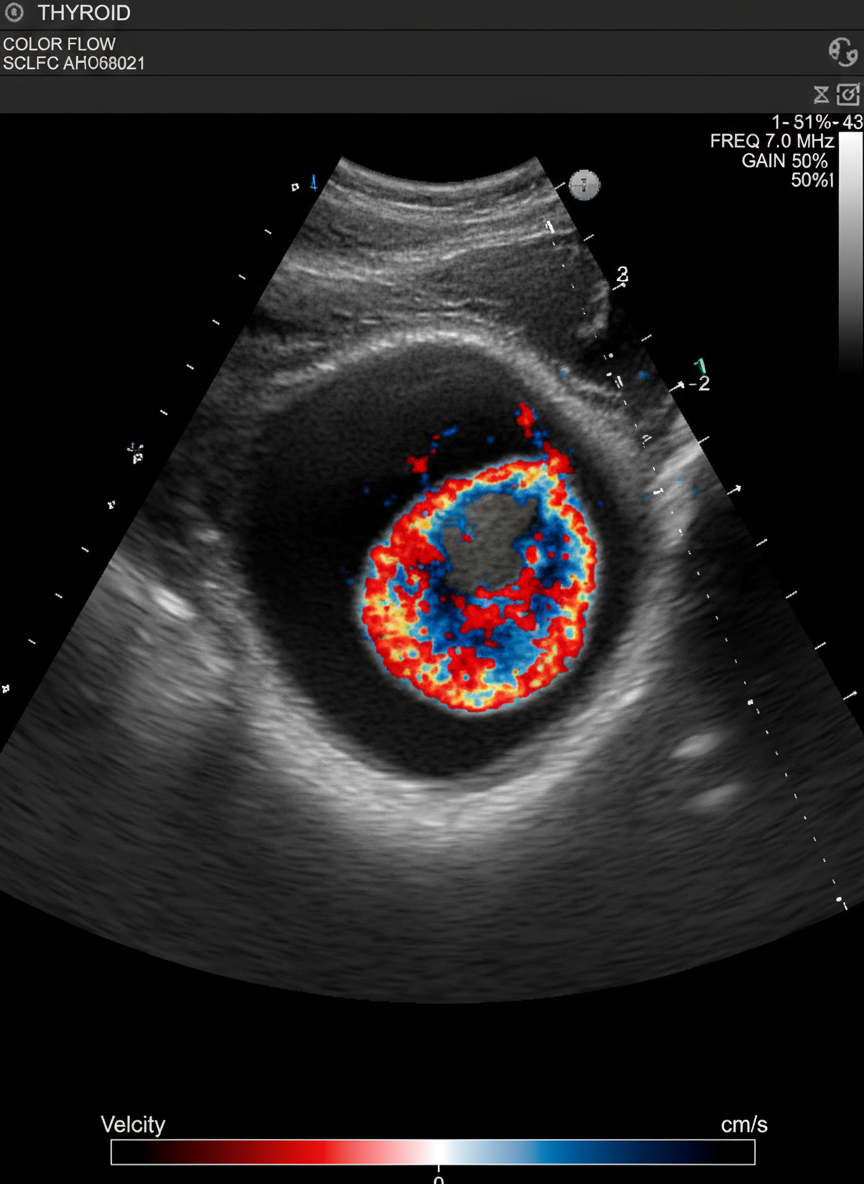

초음파 검사나 세침흡인 조직검사 같은 간단한 검사로도 충분히 확인할 수 있답니다.

갑상선암은 주로 갑상선 초음파 검사를 통해 결절을 확인하고,

의심스러운 결절이 발견되면 세침흡인 조직검사를 통해 암세포 유무를 확진해요.